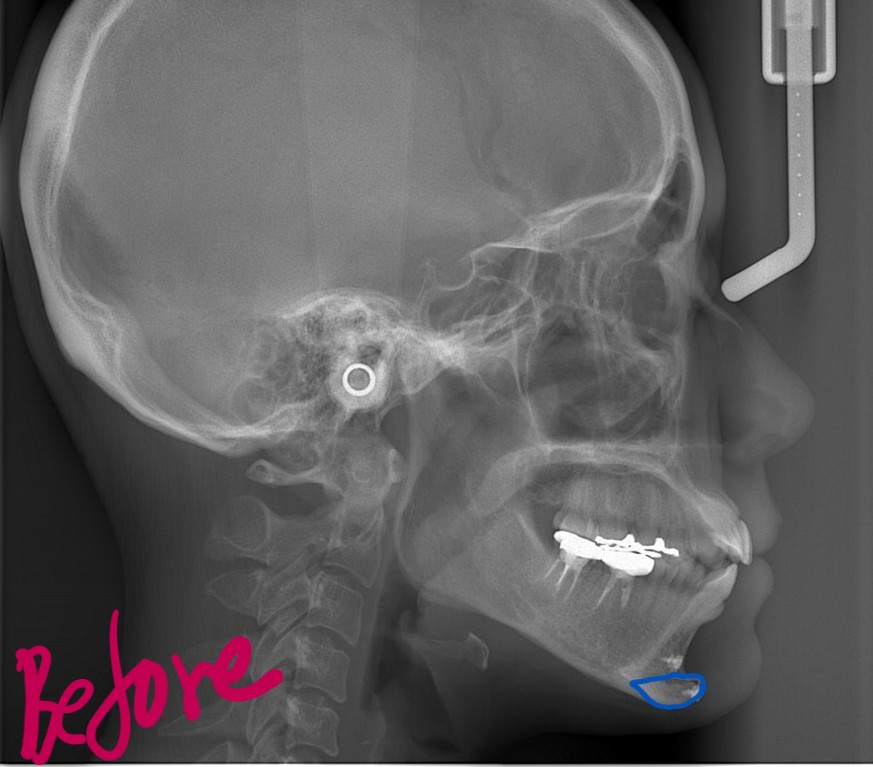

【Before】

レントゲン写真で確認すると、

一応、Eラインが引ける状態です。

この時は御縁がなく、美容外科にて(下顎の)オトガイ部に骨移植をするオトガイ形成術をされ、Eラインに整える処置をされました。

いわゆる顎は出来たのですが、緑の線で囲まれた口元の部分が出ていて、スッキリしない状況です。

また、お口を閉じるのに「力」が必要で、オトガイ部にその緊張に伴うシワが見られます。

Eラインという一点に絞れば希望はそれなりに叶ったのですが、横顔と口元という全体的なバランスで捉えると、「何か口元が出ている!」という状態でした。